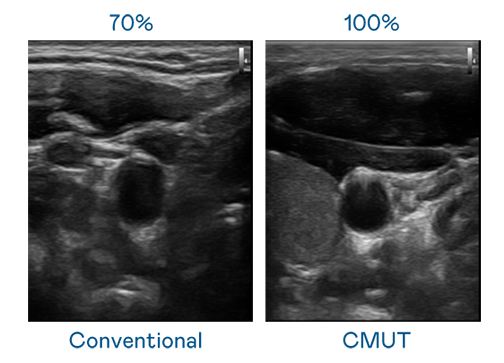

CMUT 技术是一种用电容式微机电元件来产生超音波讯号的技术。与传统 PZT 压电式技术相比,CMUT 频宽增加 30%,更宽频的超音波讯号让影像解析度大幅提升,是实现高影像品质医疗超音波扫描、促进精准医疗发展的关键技术。

大频宽带来超清晰影像

超音波影像的解析度高低,首先取决于探头能发出的讯号频宽。PA CMUT 可提供高清晰的超音波讯号,提供高频宽、高灵敏度、影像纹理细节更高的超音波影像,协助医护人员缩短影像判读时间及利用精准的医疗影像进行诊断。